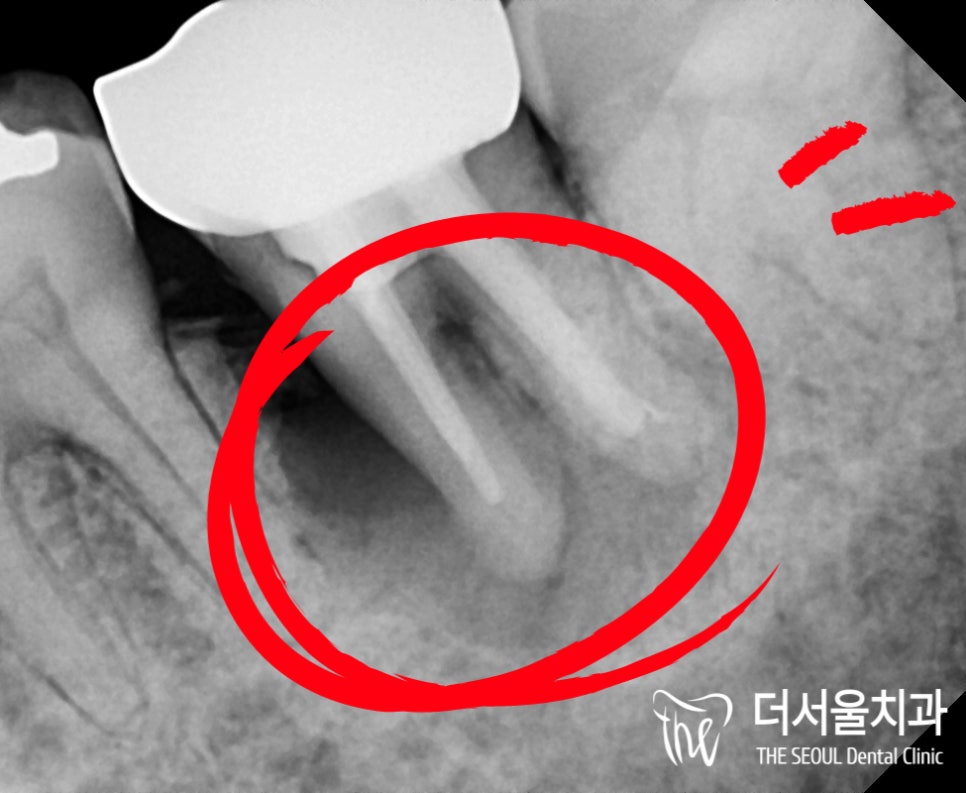

그럼 매번 더서울에서 잘하는

디지털 컴퓨터 분석 임플란트 식립 과정 및

어떻게 진행되는지 보여드려야 겠죠?

언제나 그랬듯이

디지털 컴퓨터 분석 프로그램을 이용하여

해당 위치에 임플란트를 심기 전에

뼈 두께나 깊이는 얼마나 될지,

혹시 아래 신경관과의 거리는 얼마나 될지

위치 및 각은 어떻게 하면 좋을지를

하나씩 따져봐서 좋은 결과를 만들어 드릴 수 있습니다.

그래서 네비게이션 같다는 말씀을 드린 것이죠.

차를 타서 도착지에 이동할때,

길을 알려주듯이

해당 프로그램 또한 마찬가지로

조금 더 세밀히 살펴볼 수 있게끔 도와줍니다.